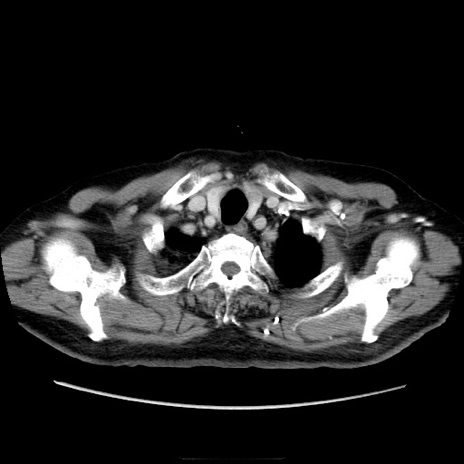

症例21(横断像)

【症例】70歳代男性

【主訴】腹痛

【現病歴】肝硬変・肝細胞癌にてかかりつけの方。約9時間前に食後より腹痛出現。症状が徐々に増悪し、嘔吐出現したため来院。

【既往歴】肝硬変、肝細胞癌(RFA、TACE後)

【身体所見】意識清明、表情苦悶様、BT 36℃、BP 129/78mmHg、P 88bpm、SpO2 97%(RA)、右上腹部から心窩部にかけて圧痛あり、反跳痛なし、筋性防御あり。

【データ】WBC 5800、CRP 0.16